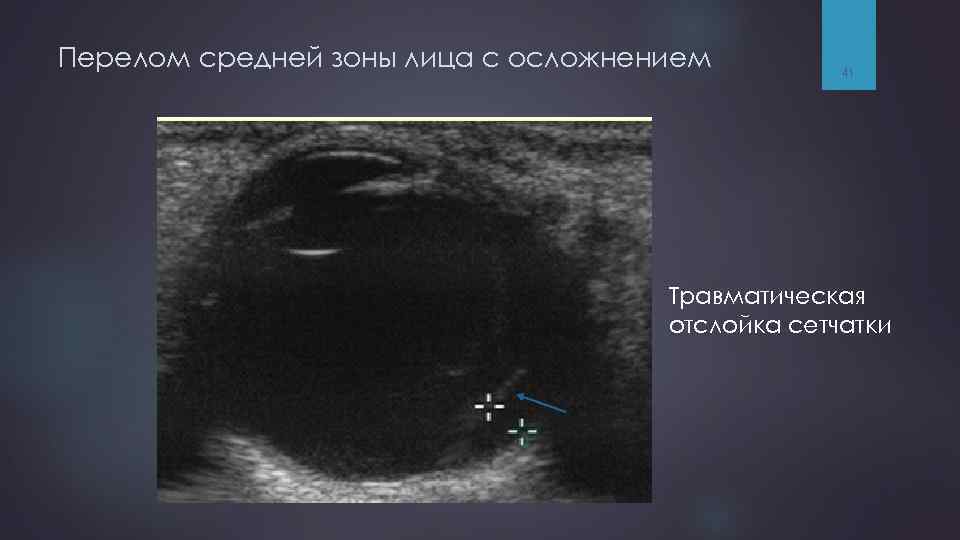

Перелом средней зоны лица с осложнением 40

Перелом средней зоны лица с осложнением 41 Травматическая отслойка сетчатки

Ультразвуковое исследование (УЗИ) УЗИ применяется для диагностики: сочетанных повреждений лицевого скелета и структур орбиты, § §позволяет §а выявить гемофтальм, отслойку сетчатки, также оценить эти состояния в динамике. Ограничением метода является невозможность оптимально оценить состояние костных структур. 77